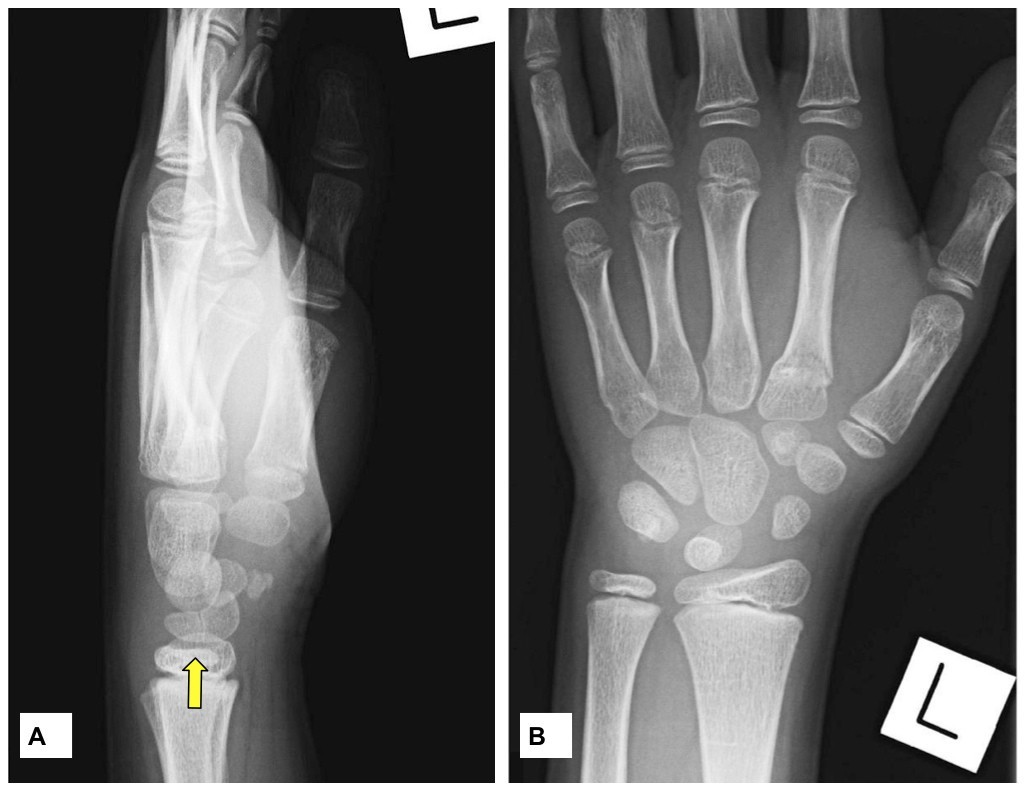

Forearm fracture in a child and complete triquetrallunate synostosis Fractured Lunate Bone Symptoms Kienbock's disease is the avascular necrosis of the lunate which can lead to progressive wrist pain and abnormal carpal motion. Kienbock’s disease is a rare bone disorder that affects the lunate, one of your eight wrist bones. Diagnosis can be made with. Given the lunate's position in the wrist, there is significant overlap from other carpal bones and hence these. Fractured Lunate Bone Symptoms.